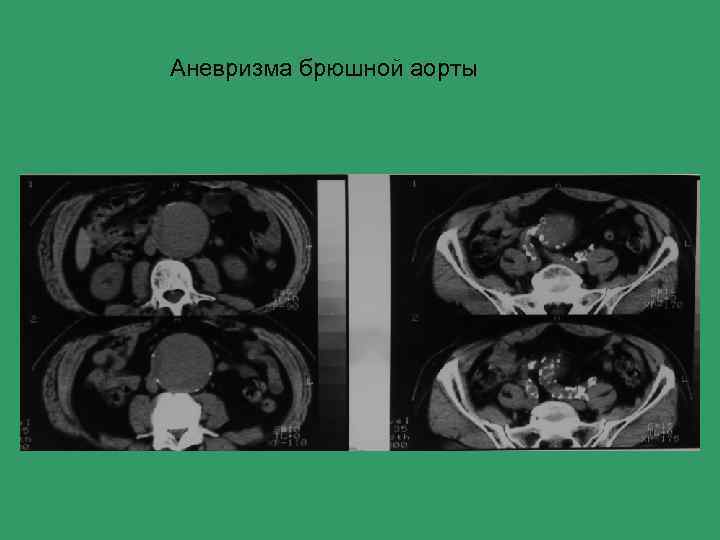

Аневризма брюшной аорты